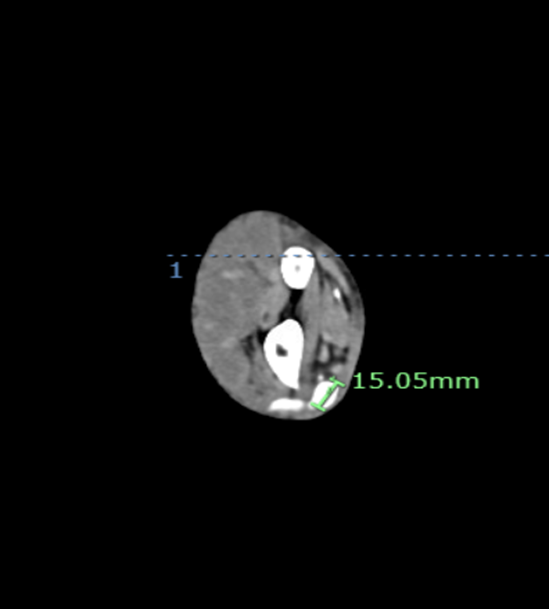

A 73-year-old man with history significant for paroxysmal atrial fibrillation on apixaban underwent percutaneous coronary intervention (PCI) of the left anterior descending artery via transradial access. The patient was discharged on clopidogrel, atorvastatin, carvedilol, isosorbide mononitrate, losartan, and apixaban. Ten days later, the patient presented with swelling in the right hand, wrist, and forearm (Figure 1). Doppler arterial ultrasound (US) showed an outpouching measuring 3.9 cm x 2.8 cm in the distal radial artery with a neck measuring 2 mm (Video). A radial artery pseudoaneurysm (PSA) was diagnosed. Before the surgical team could intervene, the PSA ruptured (Figure 2). Computed tomographic angiogram (CTA) with contrast showed 1.5 cm x 1.5 cm PSA with contrast extravasation laterally and into the dorsal soft tissues of the wrist/distal forearm consistent with hematoma and PSA rupture (Figure 3A, B). The patient underwent successful evacuation of hematoma and reconstruction of the radial artery.